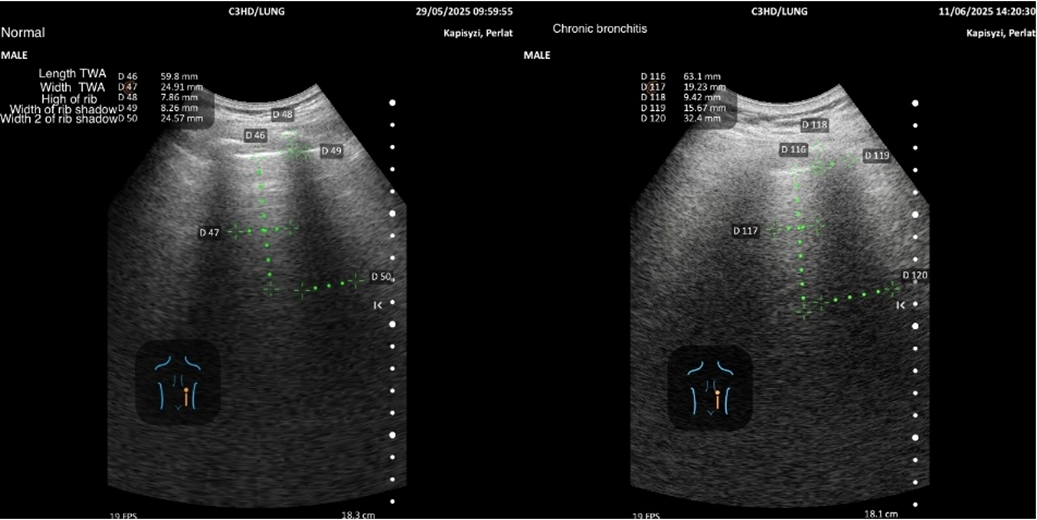

The overall project is structured in three complementary parts: (1) echographic features of emphysema compared with normal subjects, (2) chronic bronchitis compared with normal subjects (the focus of the present manuscript), and (3) emphysema versus chronic bronchitis. Representative examples of measurements by region, together with pictograms, are presented to illustrate the methodology.

The methodology for quantifying regional variables in normal subjects and bronchitis patients is illustrated with pictograms and representative examples

The cut-off values for Length TWA show regional variation. The highest positive threshold is observed in region 4, while the lowest positive threshold is observed in region 3 [Table 4, Figure 3].

The cut-off values for Length TWA inspiration show regional variation with highest positive threshold in region 2, while the lowest positive threshold is observed in region 4 [Table 7, Figure 6].

The cut off values of top five variables indicates that diagnostic performance may depend on regional lung characteristics in normal and diseased conditions [Figure 3-8].